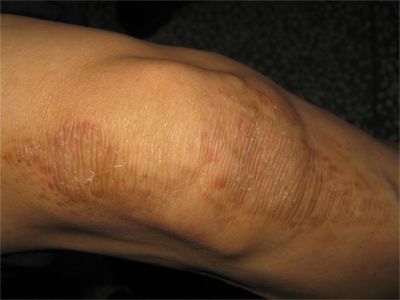

膝盖

脱屑 · 斑

扁平苔藓样接触性皮炎膝盖有褐色斑片鳞屑图

扁平苔藓样接触性皮炎患者在膝盖处可以出现片状的褐色斑块,其上有少量的薄层鳞屑,一般是由原本的红色小疙瘩融合成片发展而来,会逐渐消退。